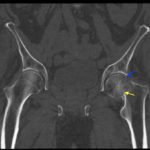

In the anteroposterior view bilateral hip x-ray, there is an evident loss of Shenton’s line on the left (red line) when compared to the normal right (white line), indicative of a fracture in the left femoral neck. This correlates with findings seen on pelvic CT, which reveals both a subcapital fracture (blue arrow) and transcervical fracture (yellow arrow). The neck of the femur is displaced superiorly relative to the head of the femur while the head of the femur remains in its anatomical position within the acetabulum.